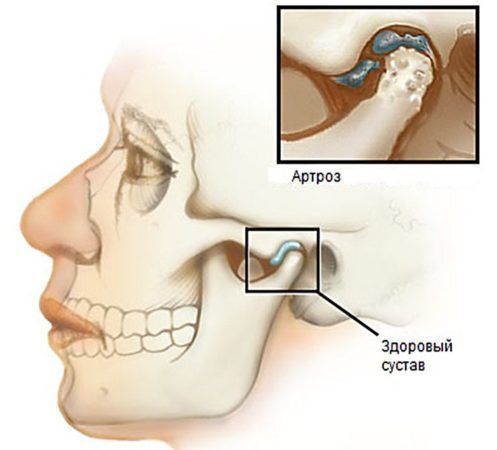

- патологии височно-нижнечелюстных суставов (ВНЧС), например артроз (ВНЧС соединяют нижнюю челюсть с основанием черепа);

Артроз ВНЧС

1. Дисфункция ВНЧС. Патология проявляется:

- хрустом, щелчками и болями в ВНЧС;

- болями и шумом в области ушей, их заложенностью и снижением слуха;

- болями при жевании, а также ограниченным открыванием рта.

Для артрогенных расстройств ВНЧС, т. е. связанных с разрушением сустава, характерны:

- шум в ВНЧС;

- боль в области сустава при пальпации (прощупывании);

- неравномерные движения нижней челюсти.

Кроме того, при движении челюсти может смещаться хрящевой диск, который защищает сустав от разрушения. Он может возвращаться на правильное место к головке мыщелкового отростка (смещение с вправлением) или оставаться смещённым (смещение без вправления). Иногда изменяются формы костной ткани в области суставного отростка (части ВНЧС). В таких случаях ВНЧС является основным источником боли, а жевание её усиливает [5].

Строение височно-нижнечелюстного сустава